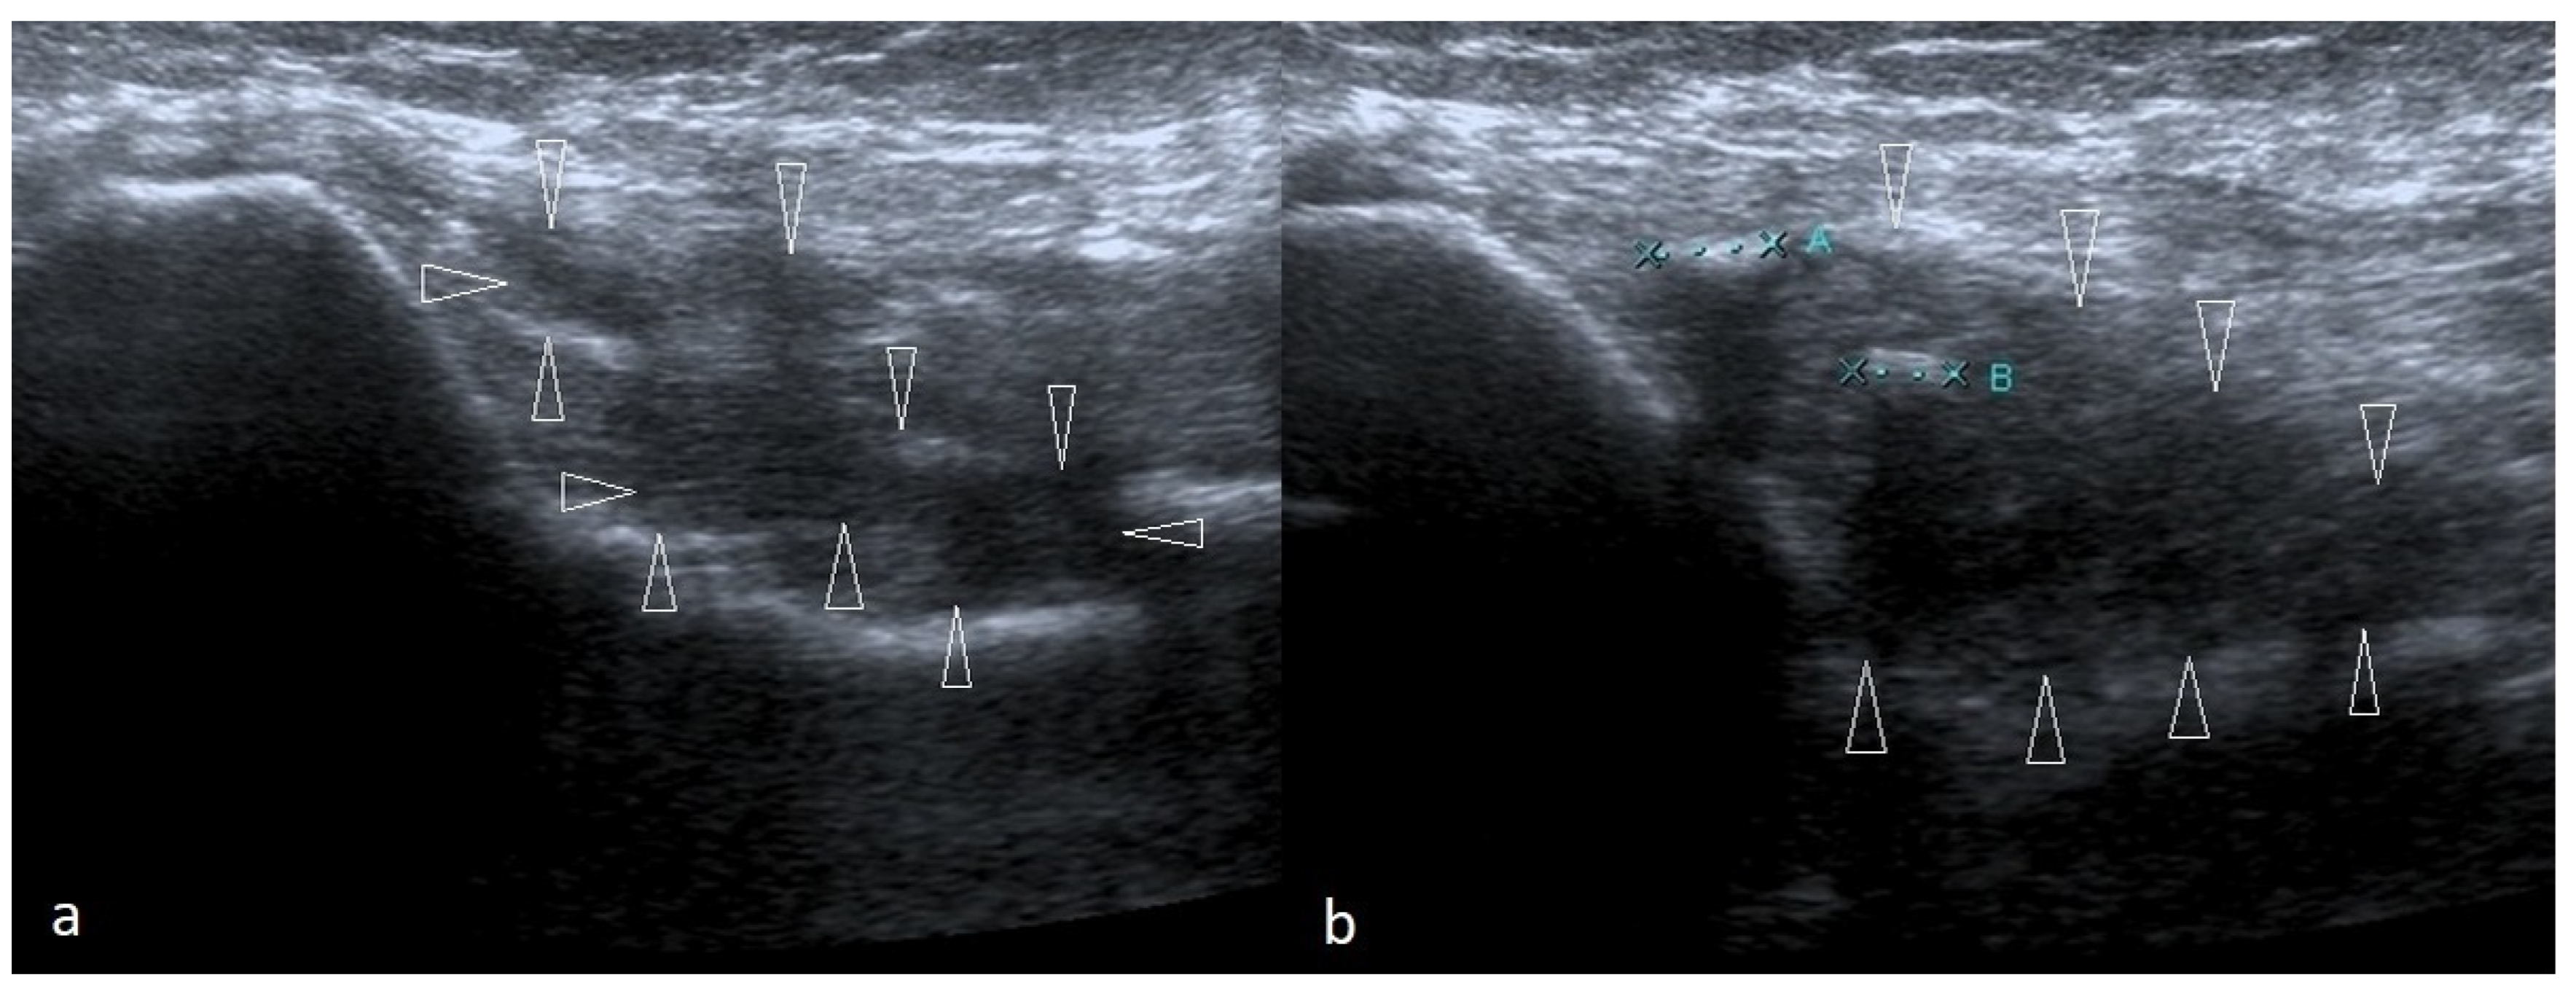

4.1. Cubital Tunnel Syndrome and Ulnar Neuritis

4.2. Snapping Triceps with Ulnar Neuritis

4.3. Ulnar Nerve Compression Caused by Anconeus Epitrochlearis